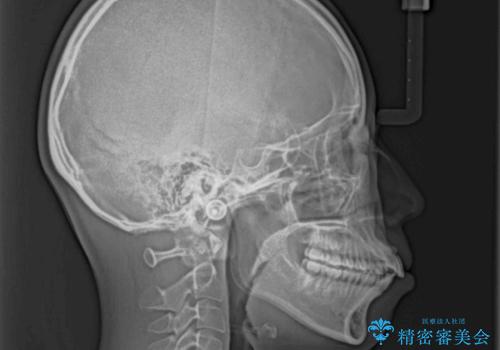

- 前歯の出っ歯と口元の閉じにくさを気にして来院された患者様です。

口元を積極的に引っ込めるために、上下左右の小臼歯4本を抜歯することとしました。

4本の歯を抜歯したことで、飛び出していた口元が引っ込み、横顔が大きく改善されました。

咬み合わせが悪化することのないようにスペースを閉じていくことができ、比較的スムーズに治療を進めることができました。